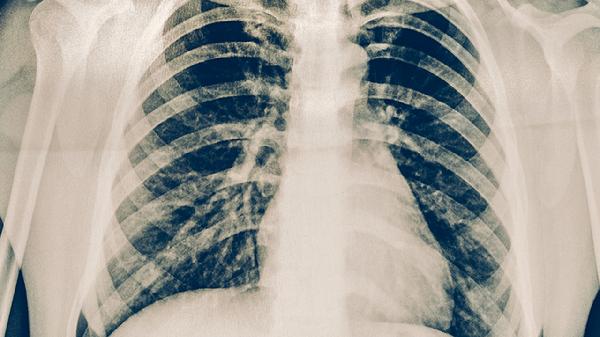

5、辅助检查:

治疗方案的选择要结合胸部X光、炎症指标CRP、PCT以及病原体检测结果。如果是支原体感染,通常首选口服大环内酯类药物;而细菌感染并伴有菌血症的话,才需要静脉用药。病情稳定后应尽快转为口服治疗。